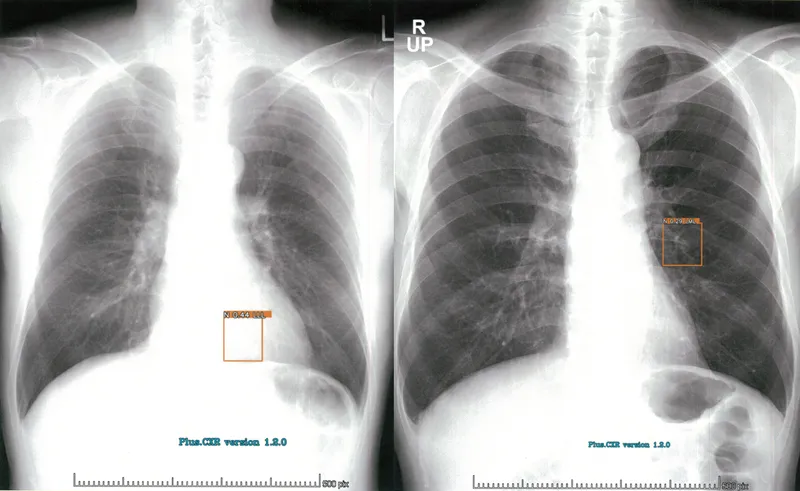

Plus.Lung.Nodule (CXR-AI)

本製品は胸部単純X線写真の読影の際に医師に診断補助となる情報を提供するAIです。

本製品はオンプレ環境にて提供され、胸部単純X線写真の読影の際に医師に診断補助となる情報を提供するAIです。

心臓や横隔膜と重なる部分も対象です AUC91~96% Cardio-Throacic Ratioを自動計測します